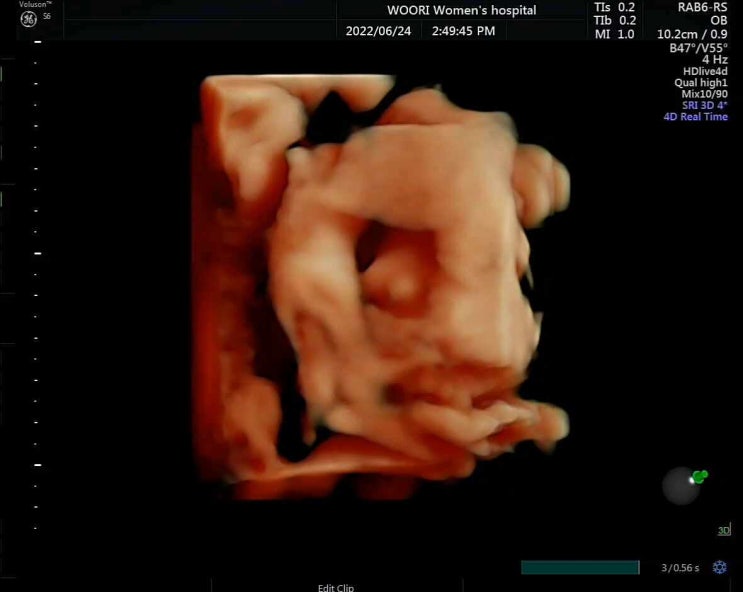

지난 정밀초음파때 팔꿈치로 심장혈관을 가리는바람에 2차정밀초음파검진을 보러갔다? 결과는 모두모두 ...